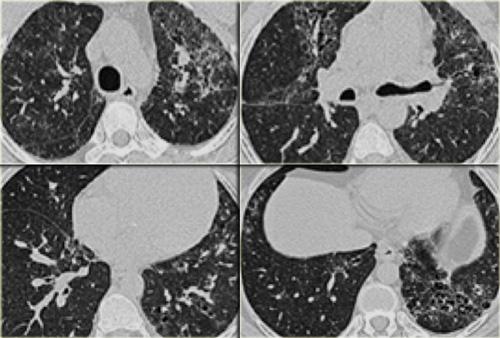

Sarcoidosis: hình ảnh điển hình với các nốt dọc theo bó mạch phế quản và các khe liên thùy. Lưu ý hạch vôi hóa một phần ở rốn phổi trái.

Dấu hiệu HRCT trong Sarcoidosis

- Dấu hiệu thường gặp:

- Các nốt nhỏ phân bố theo đường bạch huyết (dọc theo bề mặt dưới màng phổi và các khe liên thùy, dọc theo vách liên tiểu thùy và bó mạch phế quản).

- Ưu thế ở vùng trên và giữa phổi.

- Hạch to ở rốn phổi trái, rốn phổi phải và cạnh khí quản (dấu hiệu 1-2-3). Thường kèm vôi hóa.

Hình ảnh

Hình ảnh điển hình của sarcoidosis với hạch to rốn phổi và các nốt nhỏ dọc theo bó mạch phế quản (mũi tên vàng) và dọc theo các khe liên thùy (mũi tên đỏ).

Hình ảnh chi tiết với biểu hiện HRCT điển hình gồm các nốt dọc theo bó mạch phế quản (mũi tên đỏ) và các khe liên thùy (mũi tên vàng).

Đây là phân bố theo đường bạch huyết điển hình của các nốt.

Hình ảnh HRCT của sarcoidosis phổi rất đa dạng và được biết đến là có thể bắt chước nhiều bệnh phổi thâm nhiễm lan tỏa khác.

Khoảng 60 đến 70% bệnh nhân sarcoidosis có hình ảnh X-quang đặc trưng.

Trong 25 đến 30% trường hợp, hình ảnh X-quang không điển hình.

Ở 5 đến 10% bệnh nhân, X-quang ngực bình thường.

Bên trái là một hình ảnh điển hình khác của sarcoidosis với hạch to trung thất và các nốt nhỏ phân bố theo đường bạch huyết dọc theo bó mạch phế quản và dọc theo các khe liên thùy (mũi tên vàng).

Luôn tìm kiếm các nốt nhỏ dọc theo các khe liên thùy, vì đây là dấu hiệu rất đặc hiệu và điển hình của sarcoidosis.